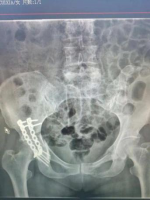

5.复杂骨盆骨折

6.髋臼骨折